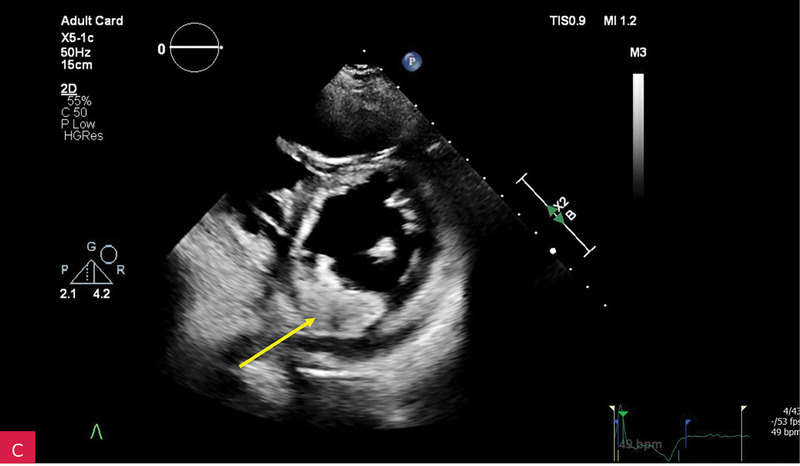

Rycina 3A-C. Badanie echokardiograficzne przezklatkowe (TTE) w osi krótkiej przymostkowej na różnych poziomach – płatków zastawki mitralnej (A), strun ścięgnistych (B) i mięśni brodawkowatych (C) – obrazuje owalną zmianę guzowatą, o dużych rozmiarach i nierównej echogeniczności, z widocznym wzmocnieniem brzeżnym